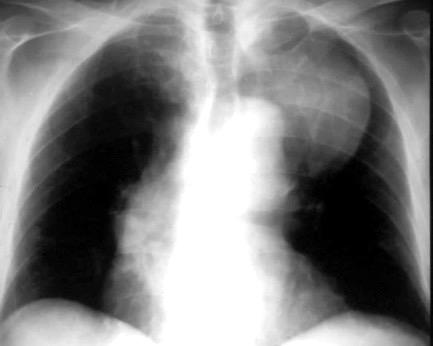

25. DERRAME PLEURAL. TRAUMA

Pancreatitis aguda.

Lesiones infradiafragmáticas

Pancreatitis. (lado izquierdo.68%)

Neoplasia gástrica/pancreática.

Ortiz-Morales CM et al. Radiology of acute pancreatitis today: the Atlanta classification and the current role of imaging in its diagnosis and treatment . Radiologia (Engl Ed) . 2019

Dahnert 2017 Pancreatitis aguda